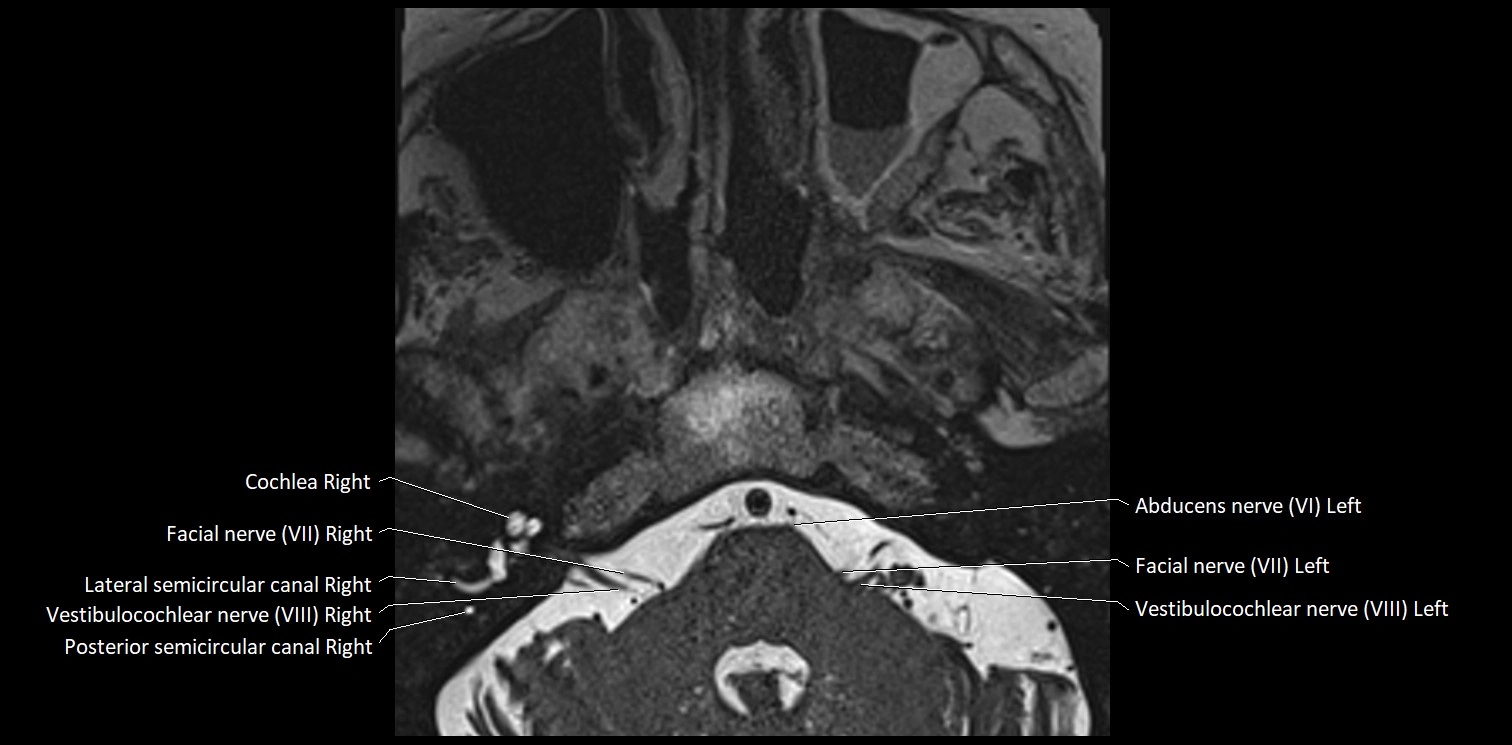

MRI Appearance

• The abducens nerve is a small, thin, linear structure

• Best visualized on high-resolution T2-weighted 3D MRI sequences (e.g., FIESTA or CISS)

• Seen as a hypointense (dark) line running from the brainstem at the pontomedullary junction, traversing the prepontine cistern, and entering Dorello’s canal under the petrosphenoidal ligament, then into the cavernous sinus, and finally the orbit

• May be challenging to visualize in standard MRI due to its small size

• Pathology may be inferred by absence, displacement, or enhancement of the nerve

MRI images

image